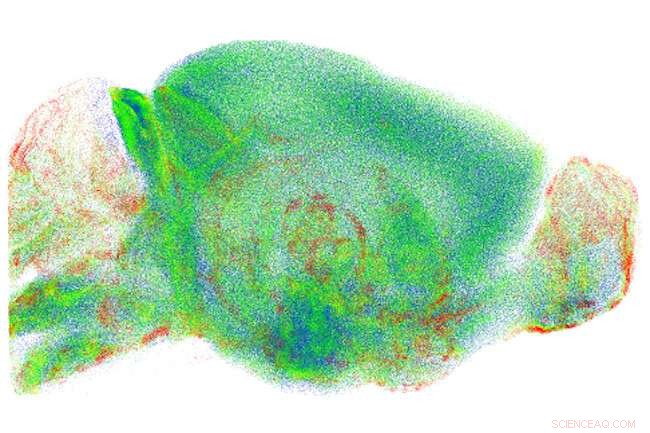

Credit: University of Glasgow

The high resolution guaranteed by RAPID—which is also the subject of an international patent owned by Unifi, the European Laboratory of Nonlinear Spectroscopy (LENS) and CNR—has allowed researchers to study on a whole-brain scale problems previously analyzed only in small, local areas.

For example, the spatial distribution of a particular type of neurons—which express somatostatin—has been investigated, showing how these cells tend to organize themselves in spatial clusters, which are suspected to make their inhibitory action more effective.

Another application concerns microglia, a set of cells with different functions (from the response to pathogens to the regulation of neuronal plasticity), whose shape changes according to the role they play. The analysis of microglia performed with RAPID revealed significant differences between various brain regions, paving the way for new studies on the role of this cell population.